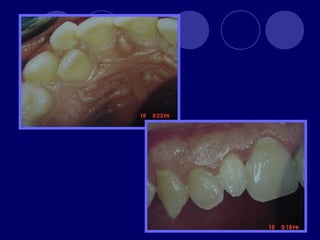

TAURODONTISMO  cuerpo deldiente se alarga, raíces cortas, furca se desplaza hacia apical, cámara pulpar amplia en sentido apico-oclusal  Dx: radiográfico  Etiología retraso en la vaina radicular de hertwing en invaginarse horizontalmente, hasta que esta cerca del ápice.  Fx: 0.5 -5 %  Se asocia a Síndromes congénitos, con herencia ligada al sexo (Sx. Klinefelter)

 Se clasificaen tres según el grado de afectación y la extensión de la cámara pulpar:  Hipotaurodontismo: leve, la corona es 1/3 total del diente, el cuello -1/3, y la raíz -2/3  Mesotaurodontismo: la raíz se divide en el tercio medio apical, la cámara pulpar es más ancha que alta, 1/3 las tres porciones  Hipertaurodontismo: la raíz se divide en el tercio ápical o no se divide, la cámara pulpar es más alta que ancha. La corona 1/3, cuello 2/3.